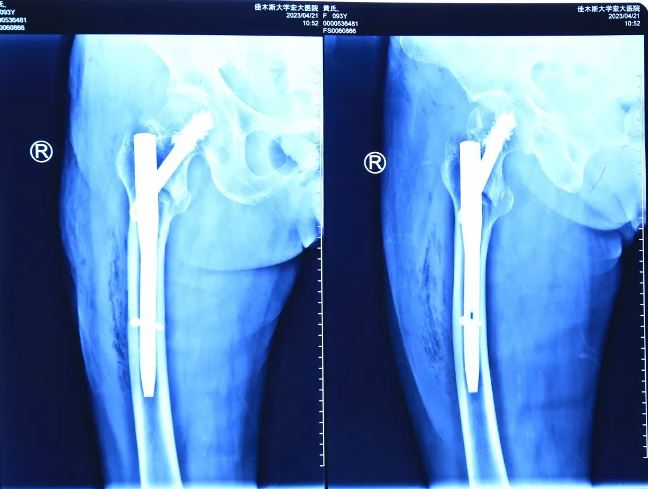

術(shù)后影像

秉著視患者如親人的態(tài)度,向患者家屬詳細(xì)解釋了病情以及并發(fā)癥可能性,并告知了高齡體弱患者手術(shù)存在的風(fēng)險(xiǎn)。根據(jù)患者病情,喬院長(zhǎng)建議為患者行右股骨粗隆間骨折閉合復(fù)位髓內(nèi)針內(nèi)固定術(shù)(APFN)。手術(shù)全程僅用不到1小時(shí),手術(shù)過程安全、無痛,固定效果良好?;颊咝g(shù)后第二天即可下地活動(dòng),患者的女兒激動(dòng)地說:“醫(yī)生,謝謝你們!真是太幸運(yùn)了,我母親可以在攙扶下站立走路了,感謝你們,是你們的精湛技術(shù),讓我的家庭再次圓滿”。

隨著醫(yī)療技術(shù)手段及綜合醫(yī)療水平的不斷提高,年齡不再是手術(shù)禁忌證。佳木斯大學(xué)宏大醫(yī)院骨科團(tuán)隊(duì)已成功救治多例85歲以上超高齡粗隆間骨折患者,充分彰顯出醫(yī)院骨科團(tuán)隊(duì)的技術(shù)實(shí)力。目前,對(duì)股骨近端骨折采取APFN髓內(nèi)釘+骨水泥加強(qiáng)固定手術(shù)這一先進(jìn)治療方法,具有手術(shù)操作簡(jiǎn)單、手術(shù)時(shí)間短、固定牢靠、對(duì)骨強(qiáng)度破壞小、出血少、骨折愈合率高等優(yōu)點(diǎn),適合于高齡股骨粗隆間骨折患者的手術(shù)要求,是一種值得推廣的骨科手術(shù)技術(shù)。